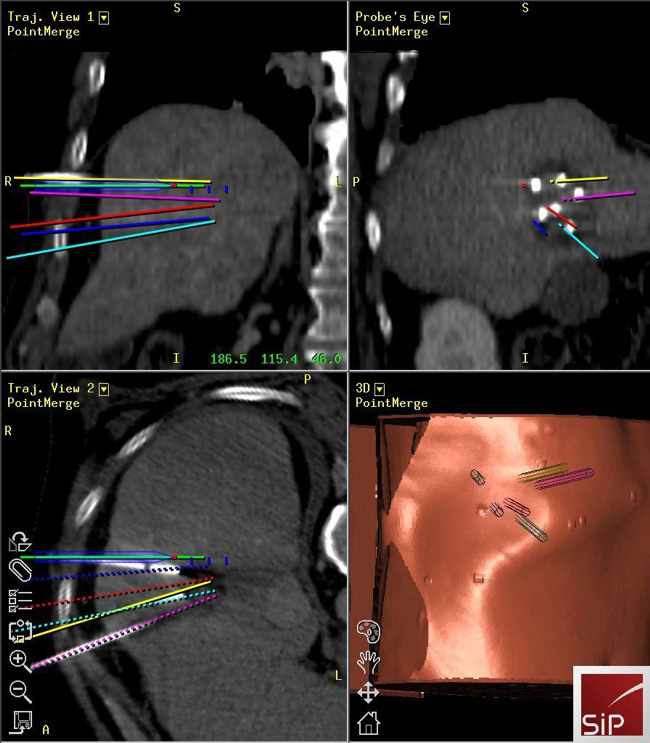

Stereotactic ablation of liver tumours:

Radiofrequency ablation (RFA) allows local curative tumour treatment by inducing coagulation necrosis with a high-frequency alternating current. The major limiting factor of conventional US- and CT- guided percutaneous single probe ablation is the tumour size. Navigation systems allow for 3D-planning of multiple overlapping ablation zones on the CT datasets and precise transformation into the real patient. We developed the worldwide first aiming device for frameless stereotactic punctures and performed the first in man stereotactic radiofrequency ablation (SRFA) of a liver tumor in 2001. Meanwhile > 1000 patients with > 3000 liver tumors, most of them being inoperable, have successfully been treated at our department.